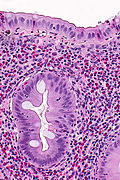

Inflammatory polyp. H&E stain. | |

| LM | polypoid shape, inflammatory cells - esp. neutrophils |

Microscopic

Features:

- Polypoid shape.

- Inflammation - esp. neutrophils - key feature.

Negatives:

- No nuclear atypia.

- May have focal nuclear hyperchromasia and nuclear enlargement.

- No dilated glands.

The sections show a fragment of colorectal mucosa with focal ulceration, acute inflammation and a well-vascularized stroma with plump stromal cells. Occasional stromal cells have nuclear hyperchromasia.

Alternate

The sections show a fragment of tissue with scant benign epithelium, acute and chronic inflammation (neutrophils and plasma cells predominantly), abundant blood vessels with reactive endothelial cells and plump stromal cells. Occasional stromal cells have nuclear hyperchromasia but do not show significant atypia.